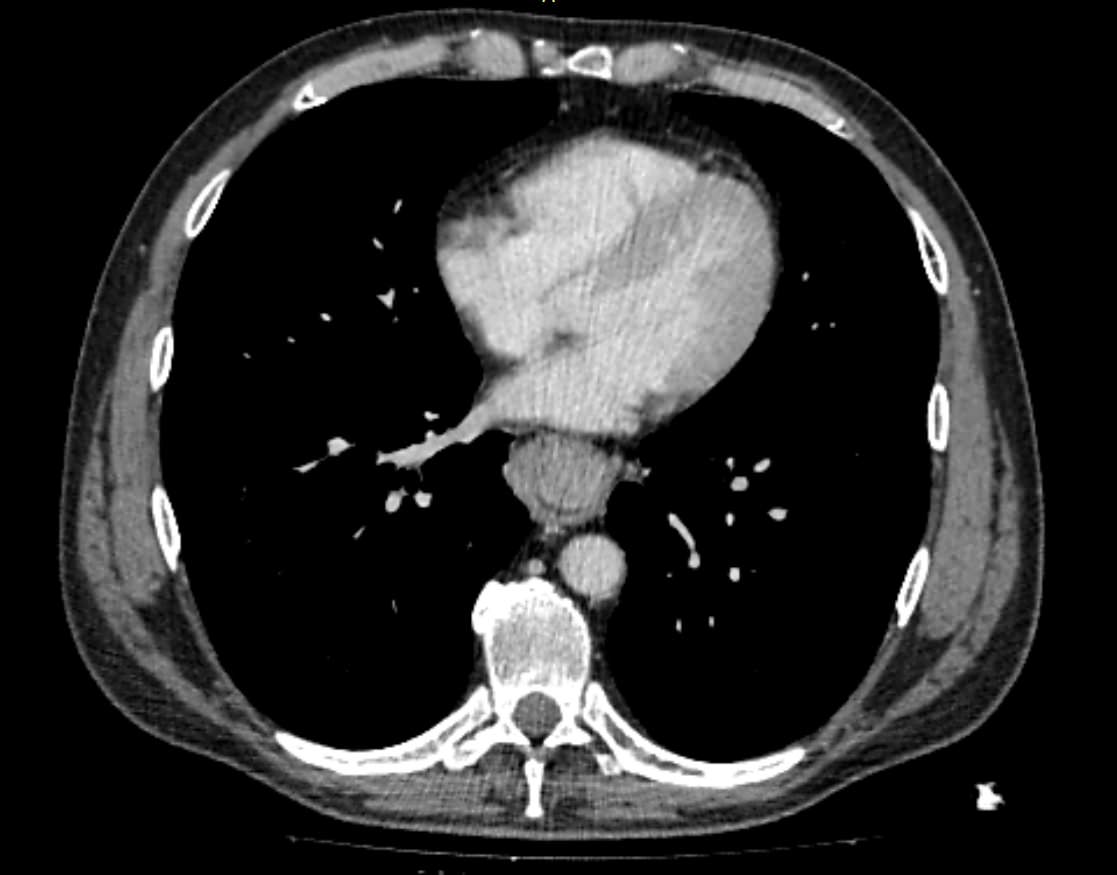

Компьютерная томография является высокоинформативным методом лучевой диагностики, который применяется для выявления заболеваний пищевода, используется при планировании оперативного лечения и для оценки успешности проведенной операции на пищеводе.

Данное исследование также позволяет оценить состояние соседних органов и тканей, включая легкие и регионарные лимфоузлы, что бывает важно для установления степени распространенности патологического процесса.

- опухоли – рак или доброкачественные новообразования (полипы, липомы, папилломы);

- кисты пищевода;

- врожденные пороки развития;

- инородные тела – в том числе те, которые вышли из пищевода в средостение (например, острые рыбьи кости);

- травматические повреждения пищевода;

- разрывы (могут быть не только травматическими, но и спонтанными);

- рубцовые сужения;

- свищи – патологические ходы, которые ведут в средостение или соседние органы, например в трахею;

- дивертикулы (выпячивания стенки пищевода);

- грыжи пищеводного отверстия диафрагмы;

- болезни оперированного и искусственного пищевода (слепой мешок, стриктуры, избыточная культя и т.д.).